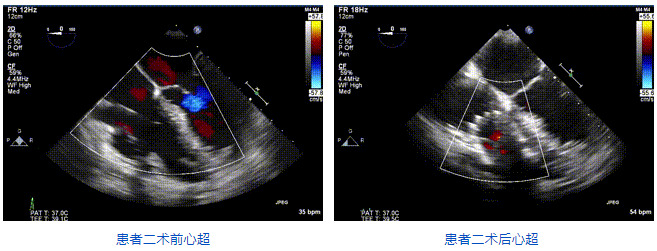

2021年12月24日,復(fù)旦大學(xué)附屬中山醫(yī)院葛均波院士團(tuán)隊(duì)成功應(yīng)用LuX-Valve Plus為一例極重度三尖瓣反流(TR)合并房顫、房缺的患者完成了經(jīng)血管三尖瓣置換術(shù),這是在前基礎(chǔ)上,本周完成的第三例經(jīng)血管三尖瓣置換手術(shù),葛均波院士、周達(dá)新教授等與心外科魏來教授、賴顥教授,心超室的潘翠珍教授、李偉教授及麻醉科的郭克芳教授共同完成了本周手術(shù),均獲得圓滿成功!患者術(shù)后超聲顯示無TR,臨床癥狀明顯改善。本周手術(shù)的成功也為LuX-Valve Plus救治性臨床研究添上了濃墨重彩的一筆。

本周三例接受LuX-Valve Plus經(jīng)血管三尖瓣置換術(shù)的患者中,第一例患者為冠狀動脈旁路移植術(shù)+Bentall+二尖瓣成形術(shù)后;第二例患者為永久起搏器植入術(shù)后,存在跨三尖瓣導(dǎo)線;第三例患者合并房顫、房缺及左心耳封堵術(shù)后。

三例患者入院后,葛均波院士團(tuán)隊(duì)周達(dá)新教授、潘文志教授、張?jiān)床┦?、陳莎莎博士及心超室的潘翠珍教授、李偉教授對患者的情況進(jìn)行詳細(xì)評估和討論,最終決定為三例患者選擇LuX-Valve Plus40mm、50mm和50mm型號的瓣膜進(jìn)行手術(shù)治療。手術(shù)后即刻拔除氣管插管,術(shù)后患者三尖瓣反流癥狀得到顯著改善,復(fù)查心超結(jié)果顯示人工三尖瓣瓣膜支架固定穩(wěn)定,瓣葉關(guān)閉形態(tài)未見異常,未見明顯反流。